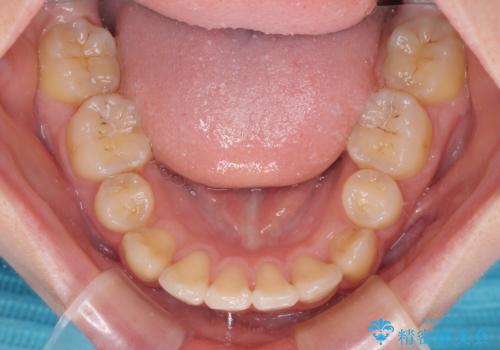

その後スペースを閉じるために時間を要しましたが、満足のいく仕上がりとなりました。